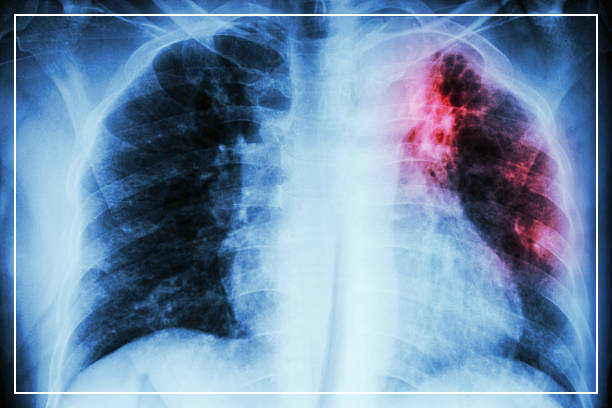

일반적으로, 결핵 검사와 흉부 X선 검사가 사용됩니다.

흉부 X선 검사는 폐에 결핵균에 의한 염증이 있는지 여부를 확인하기 위해 촬영을 수행합니다.